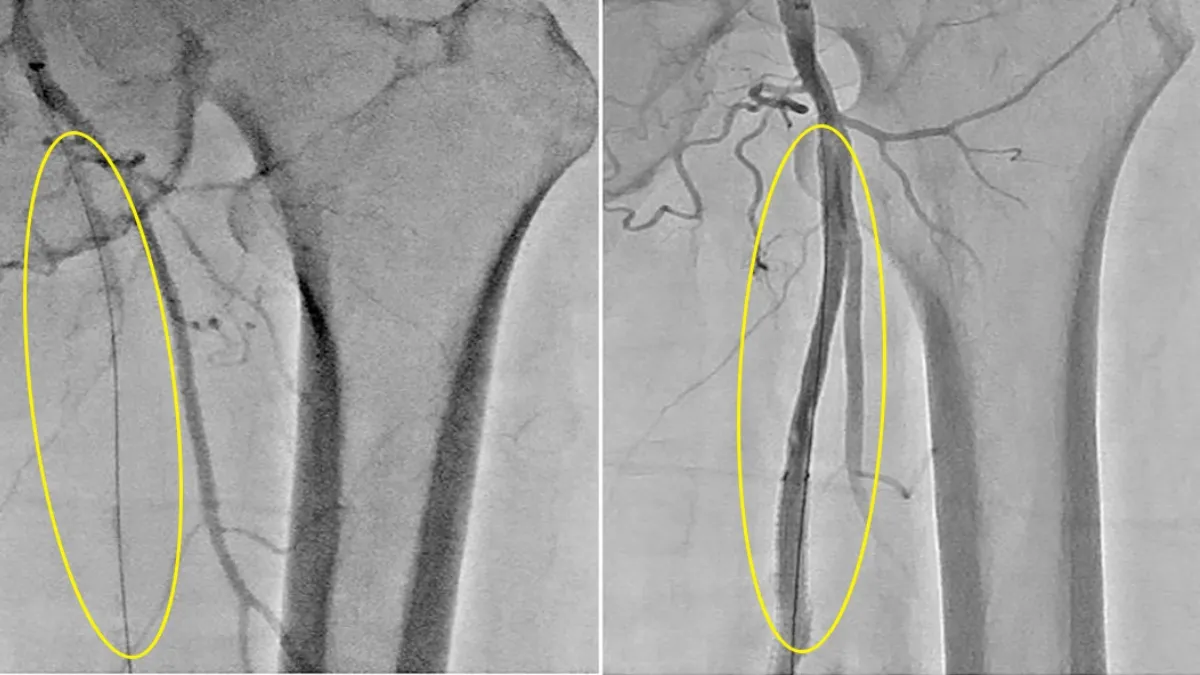

考量患者年事已高且合併慢性病,傳統外科血管繞道手術風險較高,大面積傷口的癒合也是一大考驗。張耿豪決定實施「微創經皮血管成形術」,僅在鼠蹊部開啟一個如打針般的微小穿刺傷口。醫師透過導管進入血管,利用「旋轉式斑塊切除系統」清除厚重且硬化的斑塊,再輔以支架撐開血管。血管攝影顯示,術前幾近斷流的血管在術後已恢復穩定血流。